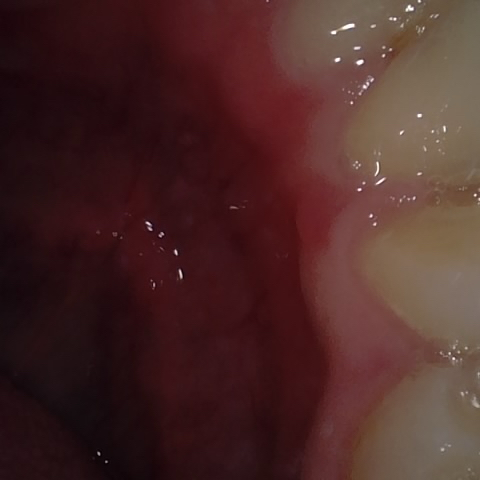

Annotated as "Bad"